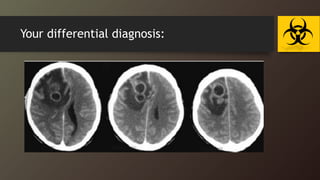

Case :30 d/o boy FT , NSVD with history of Abnormal

movement for one day (tonic colonic focal seizure)

Your differential diagnosis:

Case :30 d/oboy FT , NSVD with history of Abnormal movement for one day (tonic colonic focal seizure)

• 36.

• 37.